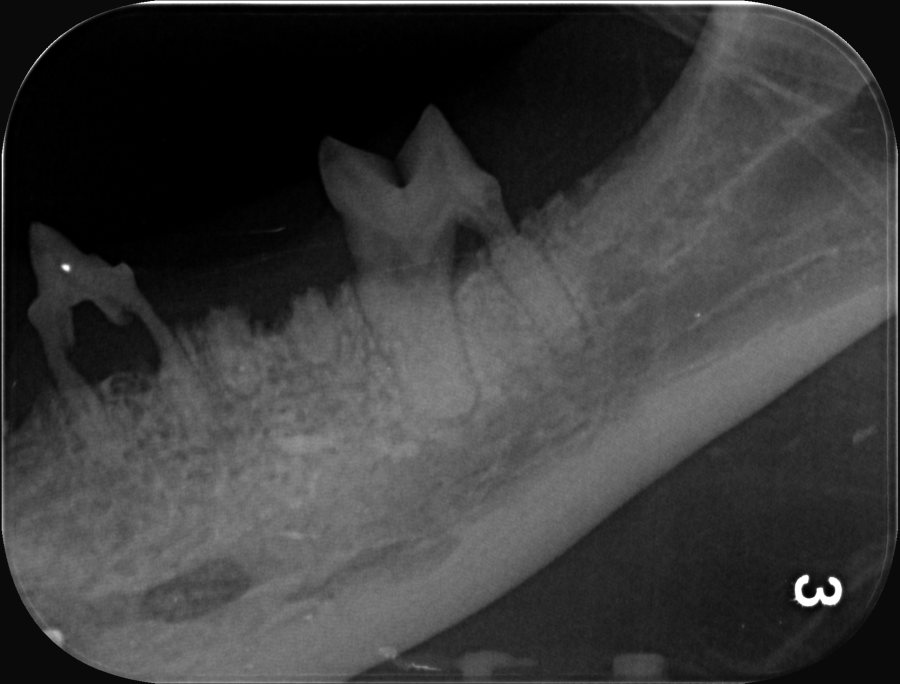

Zahnsanierungen bei Katzen werden grundsätzlich nur mit digitalem Röntgen aller Zähne und Zahnwurzeln durchgeführt, da vor allem Katzen sehr oft schmerzhafte Veränderungen der Zahnwurzeln haben, die nur im Röntgenbild zu sehen sind.

Zähne werden bei uns in der Regel offen extrahiert um sicher die kleinen, fragilen Wurzeln zu entfernen und keine schmerzhaften Reste im Zahnfach zu belassen. Dafür wird das Zahnfleisch "geflapt" = freipräpariert und hochgeklappt, das Zahnfach mit einem Bohrer aufgesägt und mehrwurzelige Zähne mit einem Bohrer zerteilt und vorsichtig entfernt. Danach alles wieder geglättet und das Zahnfleisch wird mit einer Naht über der offenen Zahnwunde vernäht.